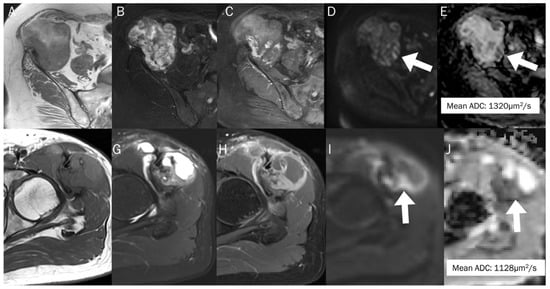

7.3. Benign Bone and Soft Tissue Tumors

7.4. Vertebral Endplate Changes